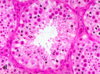

When looking histologically where would you find sertoli and leydig cells?

- Sertoli cells have large nucleus

- Leydig cells in interstitium